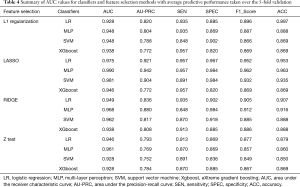

Performance of CT radiomic model in differentiating between COVID-19 and CAP

Sixteen models were established in this study. For each model, the evaluation metrics were AUC, the area under the precision-recall curve (AU-PRC), sensitivity (SEN), specificity (SPEC), F1-score, and accuracy (ACC). Table 4 summarizes the varying performance of each model for each classifier concerning the different feature selection methods. Among all the models, the Lasso regression yielded higher AUC values for all used classifiers. Notably, the MLP classifier obtained the highest AUC of 0.990 [95% confidence interval (CI): 0.962–1.000]. The results indicated that combining the LASSO with the MLP classifiers resulted in the best-performing model with the highest ACC (96.3%), SEN (95.7%), SPEC (98.4%), and AU-PRC (0.942) (Figure 3).

Full table

Conventional radiomics models were developed and evaluated concerning different feature selection algorithms and classifiers to identify COVID-19. Among the 16 different combinations, Lasso regression with MLP was the most predictive classifier with an AUC of 0.990 (95% CI: 0.962–1.000). This predictive accuracy was comparable to the DL models proposed by Li et al. (AUC =0.96 for COVID-19) and Song et al. (AUC =0.98 at the image level and 0.99 at the patient level) (7,21). Unlike the DL CAP algorithm, which requires a significant amount of labeled data for training and validation, our proposed model enabled binary classification using features derived from DL-based segmentation masks reviewed by humans. The involvement of a human factor maximizes the success of developing algorithms powered by DL in radiology.